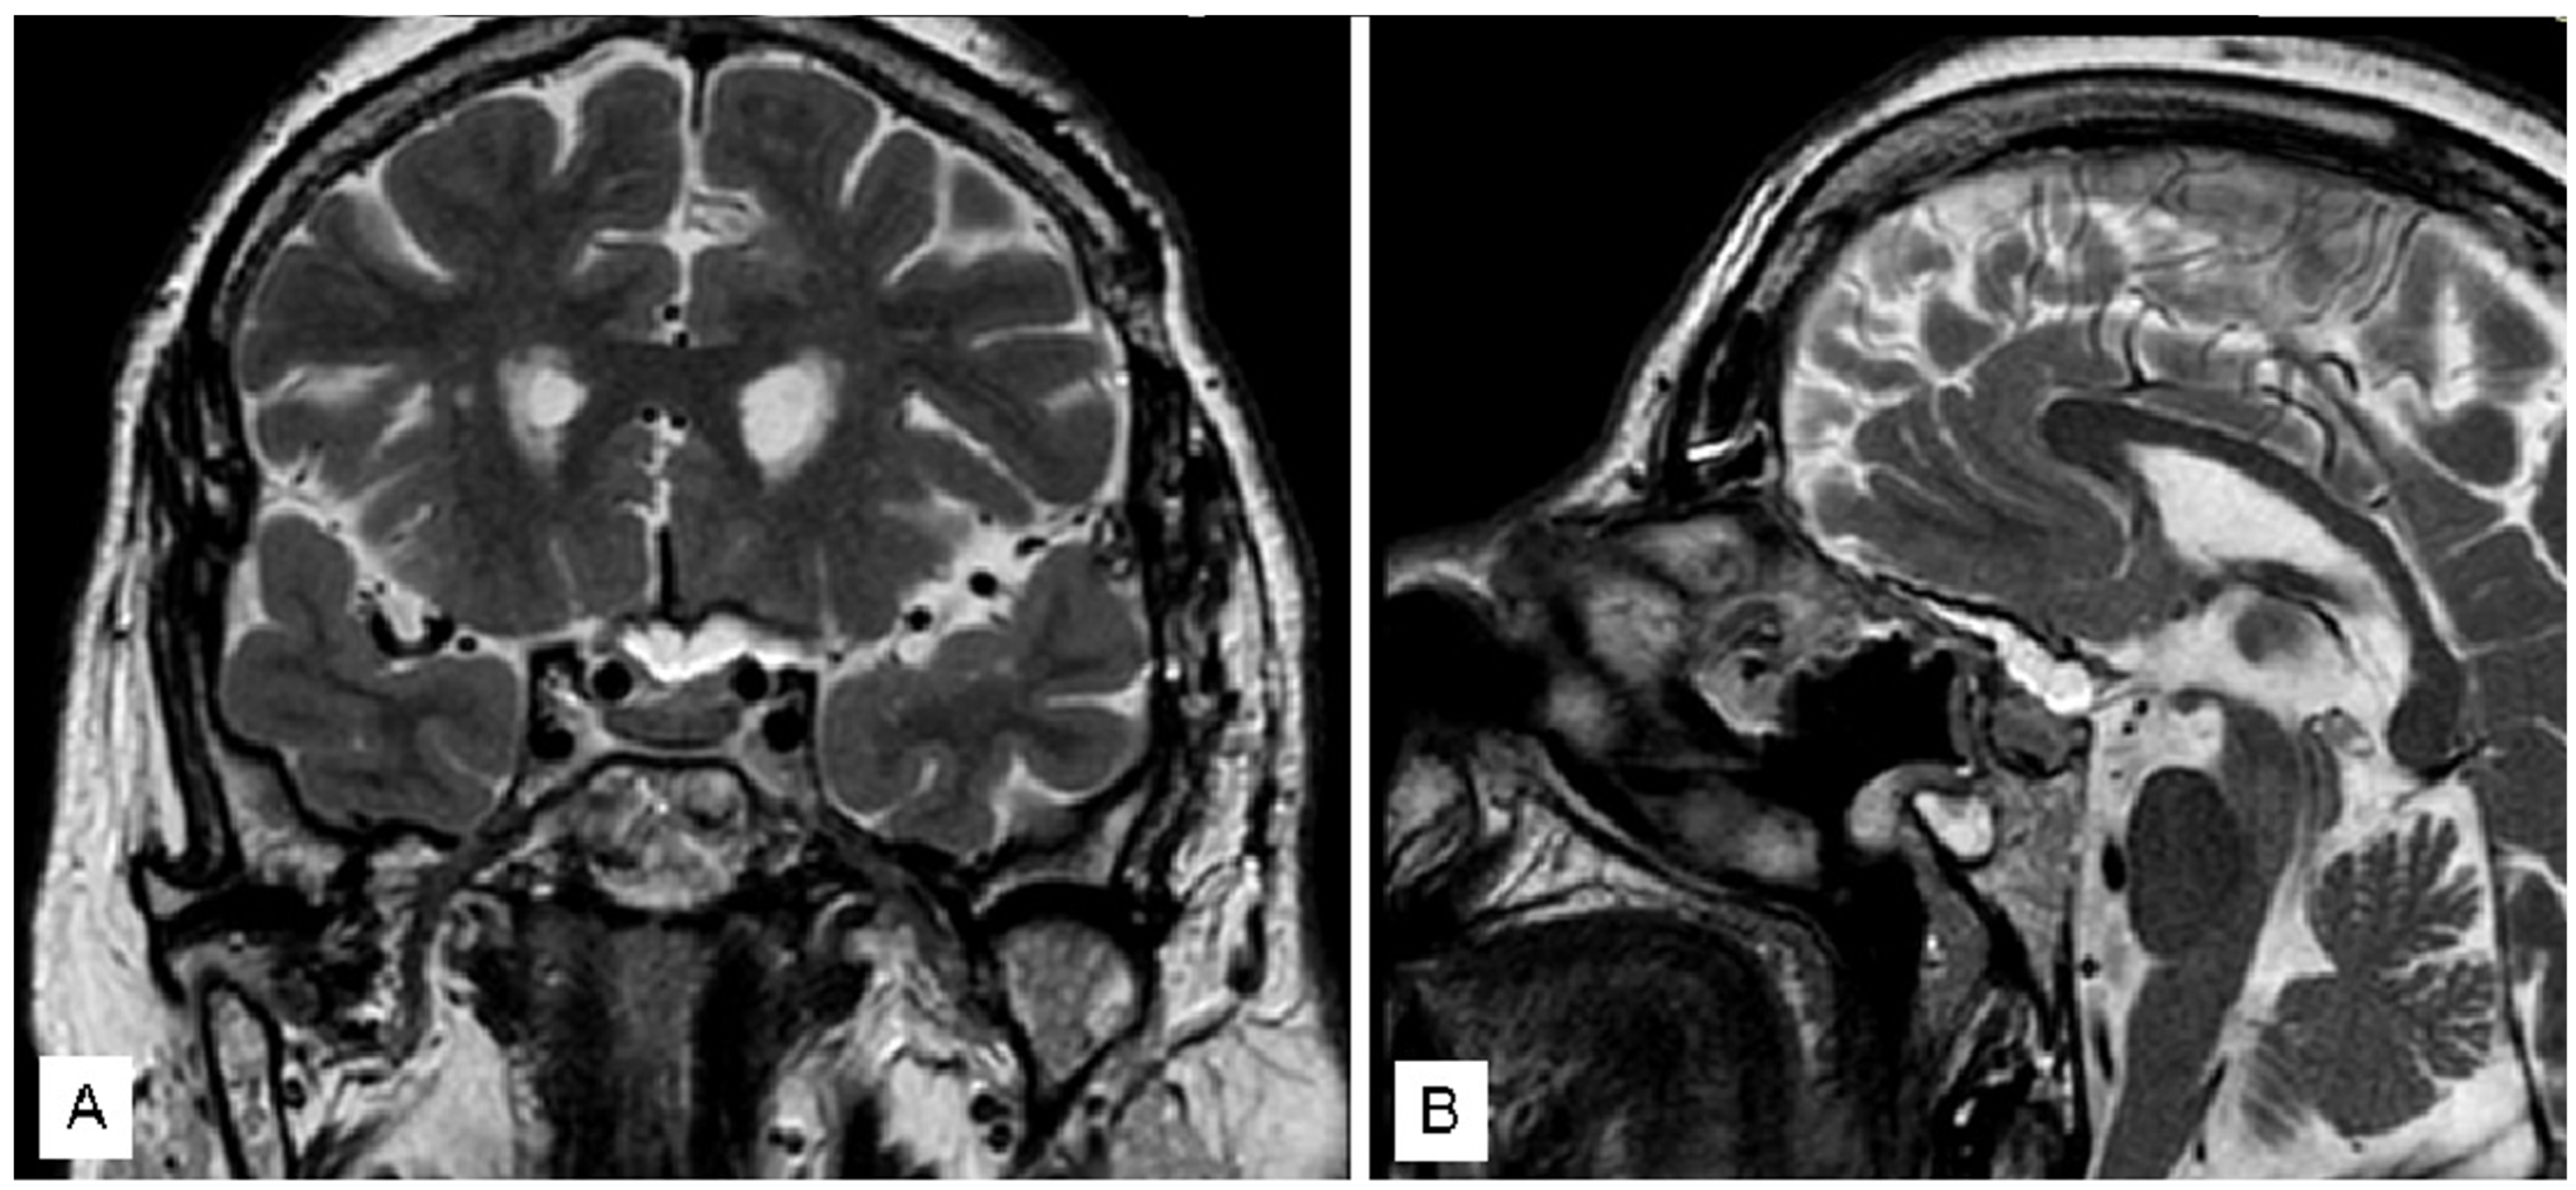

3.1.1. Case 1

3.1.2. Case 2

3.1.3. Case 3